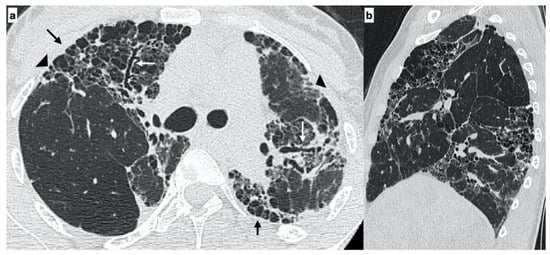

At diagnosis, there was a statistically significant difference in the HRTC pattern between the two groups: sporadic IPF patients had a predominantly typical UIP pattern compared to familial IPF patients (60.0% vs. 21.1%, respectively). There was a predominance of an alternative diagnosis HRTC pattern in familial IPF compared to sporadic IPF (31.6% vs. 2.2%, respectively) (see Figure 1, Figure 2 and Figure 3). The HRCT for 6/19 patients with a familial pulmonary fibrosis at the onset of symptoms had an alternative diagnosis pattern: this was due to the presence of a fibrotic nonspecific interstitial pneumonia (NSIP) pattern in 4/19 patients, whilst in 2/19 patients it was due to the presence of honeycombing with upper-mid lung distribution (see Figure 1). At the onset of symptoms, only 1/46 sporadic IPF patients had an alternative diagnosis HRCT pattern, due to the presence of honeycombing with upper-mid lung prevalence and mosaic attenuation; the definitive diagnosis of IPF was made by biopsy (see Figure 2 and Figure 4). After 2 years from diagnosis in the familial IPF group, we observed a slight increase in the typical UIP pattern at HRTC evaluation (see Figure 3 and Figure 5).

Figure 4. A 67-year-old male with “UIP pattern” on HRCT at the onset of respiratory symptoms. Axial HRCT plane shows honeycombing (black arrows) and reticulations (arrowheads) with a basal predominant distribution (a); traction bronchiectasis (white arrows) and distribution of alterations are better visible on the sagittal plane (b). Genetic analysis demonstrated the following types of mutations: SFTPA2, promoter-TERT, TERT.